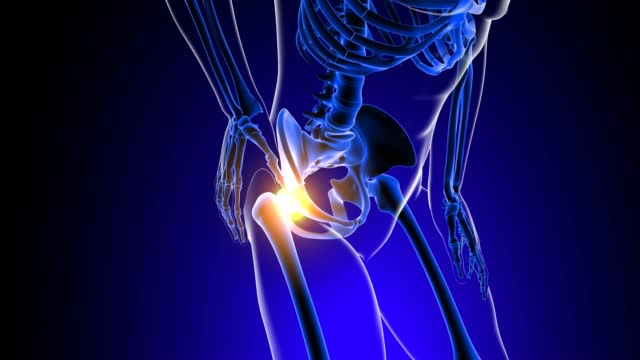

고관절 통증 증상 치료와 관리

고관절 통증을 관리하고 치료하기 위해서는 다양한 요인을 고려해야 합니다. 통증을 완화하고 원인을 해결하기 위해 개별 환자에게 맞춤형 치료 계획이 필요합니다. 이때, 관절과 근육의 조화로운 기능을 회복시키기 위한 재활운동이 중요합니다.

고관절 통증 증상 예방

고관절 통증을 피하기 위해서는 예방이 중요합니다. 특히, 허리와 고관절을 지지하는 근육을 강화하는 운동은 큰 도움이 됩니다. 이러한 운동은 40대부터 시작하여 허리와 관절의 건강을 유지하는 데 도움을 줄 수 있습니다.